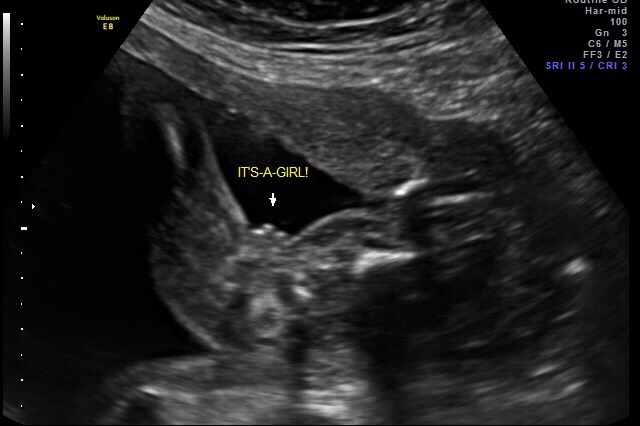

Hi ladies need some help. Is this 100% a girl. Had a few friends say it looked like boy partsAttachment 26438

This was at my 20 week anatomy scan.

No.. that's a girl. I'd be shocked if she turned out to be a he! How many weeks are you here?

Yeah, at 20 weeks that's definitely a girl!

Girl